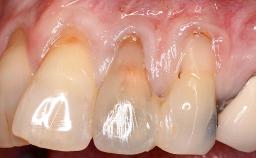

Periodontal Plastic Surgery and Prosthetic Procedures to Treat Peri-Implant Soft-Tissue Dehiscences

A 30-year-old woman was referred by her general dentist for evaluation of an esthetic complication related to previous implant treatment for congenitally missing maxillary lateral incisors. The patient’s chief complaint was the inadequate esthetic appearance of her smile. The case demonstrates the use of a combined approach to achieve optimal results. Two different flap designs - a tunnel technique and a coronally advanced flap - are employed based on the surgical objectives for the affected site.

Soft Tissue Anatomy Intact Defective